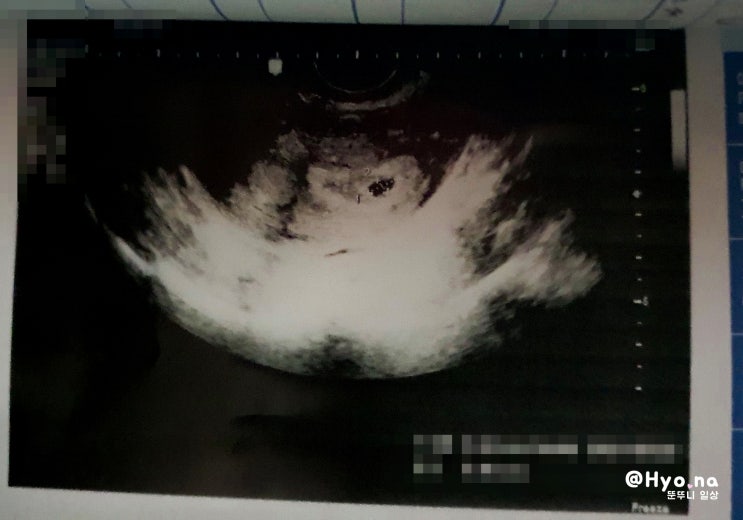

임신초기증상, 어느 날 갑자기 내게 온 별 이야기

한동안 연애에 빠져 포스팅을 미루고 결혼 후 세계 여행을 한다고 미루고 매일 요리에 집안일을 하고 나니 ...